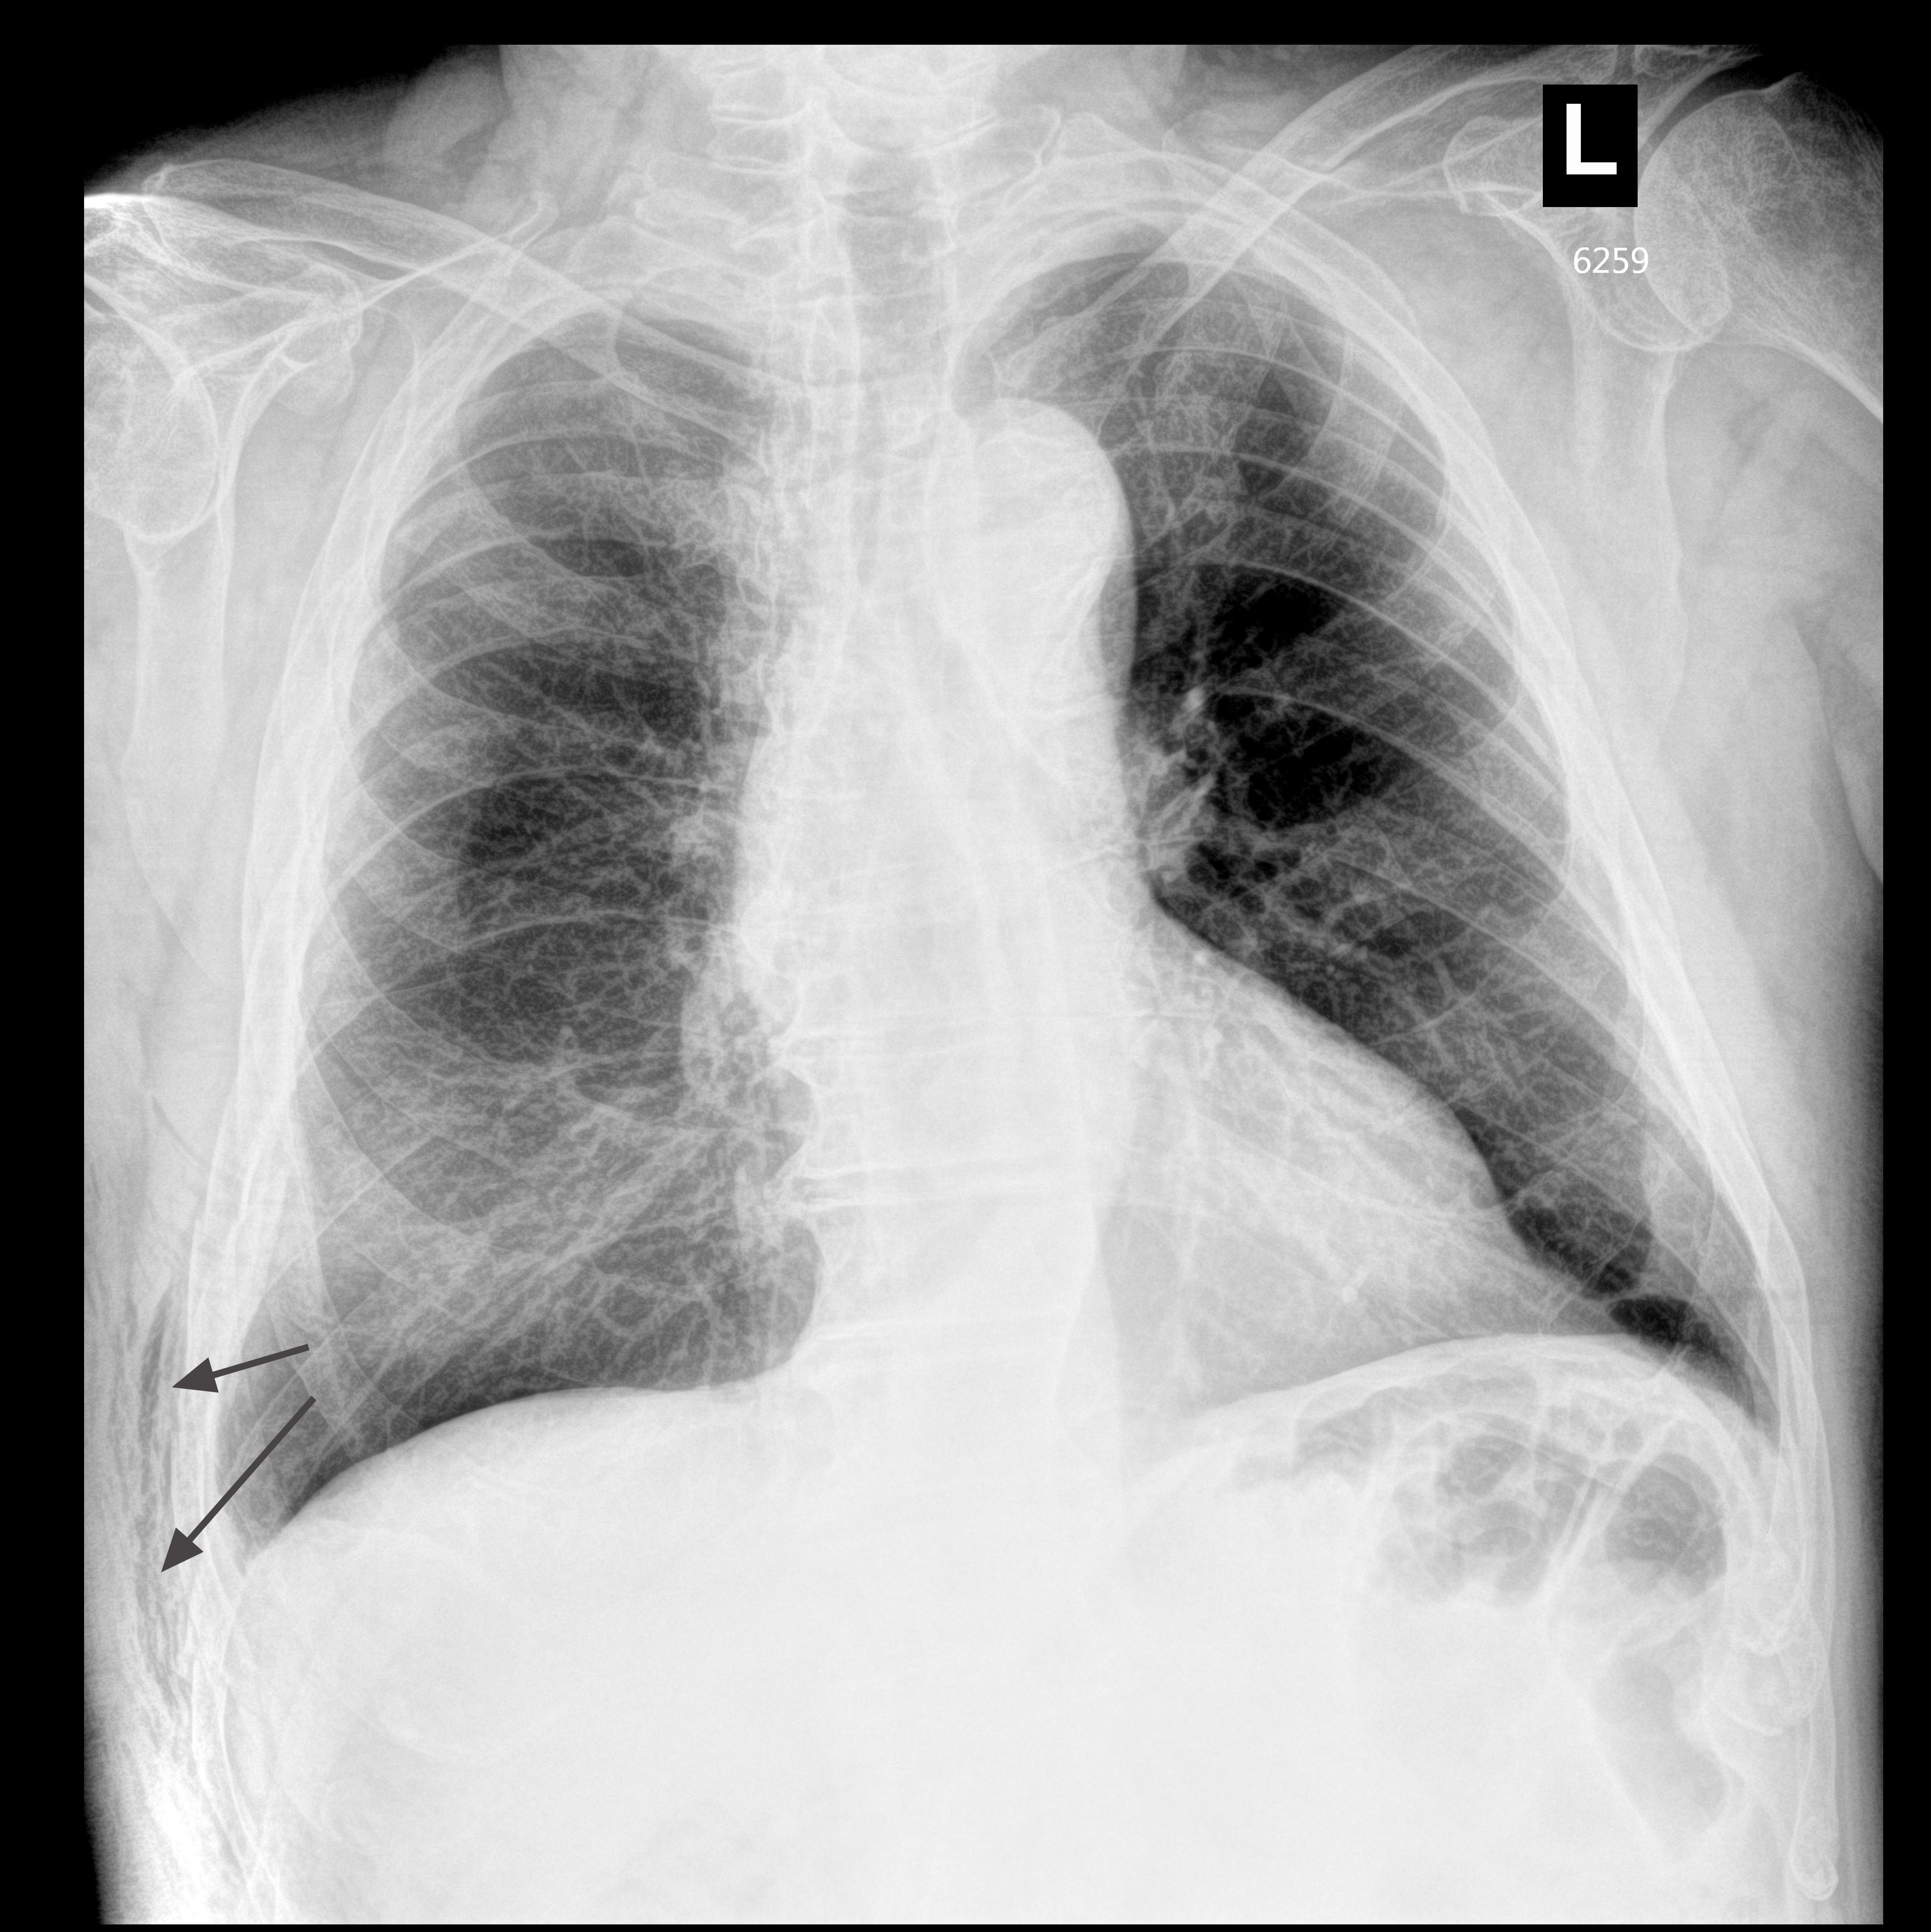

Пожилой человек, упал с лестницы в саду. Жалобы на сильные боли в грудной клетке и пояснице справа. Одышки нет.

Отправлен на рентгеновское исследование грудной клетки.

На рентгенограмме определяется воздух в мягких тканях, данных за массивный пневматоракс нет.